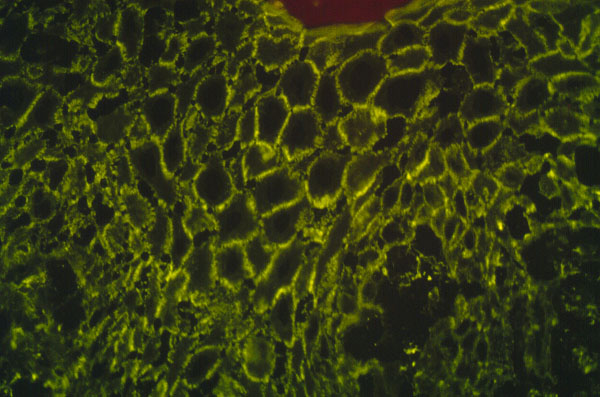

The edge of a blister with intact surrounding normal skin, uninvolved skin adjacent to a blister, or adjacent erythematous skin should be supplied for study. The tissue may be snap-frozen or transported in Michel’s medium. DIF testing is a very reliable and sensitive diagnostic test for pemphigus vulgaris, in that it demonstrates lacelike IgG in the squamous intercellularlcell surface areas in up to 95% of cases, including early cases and those with very few lesions, and in up to 100% of cases with active disease . It remains positive, often for many years after clinical disease has subsided. In late lesions, when acantholysis is well developed, the lacelike intercellularlcell surface pattern of IgG may become dotlike, paralleling electron microscopic findings and correlating with aggregation of desmosomes on the cell surface. Negative DIF findings when the patient is in